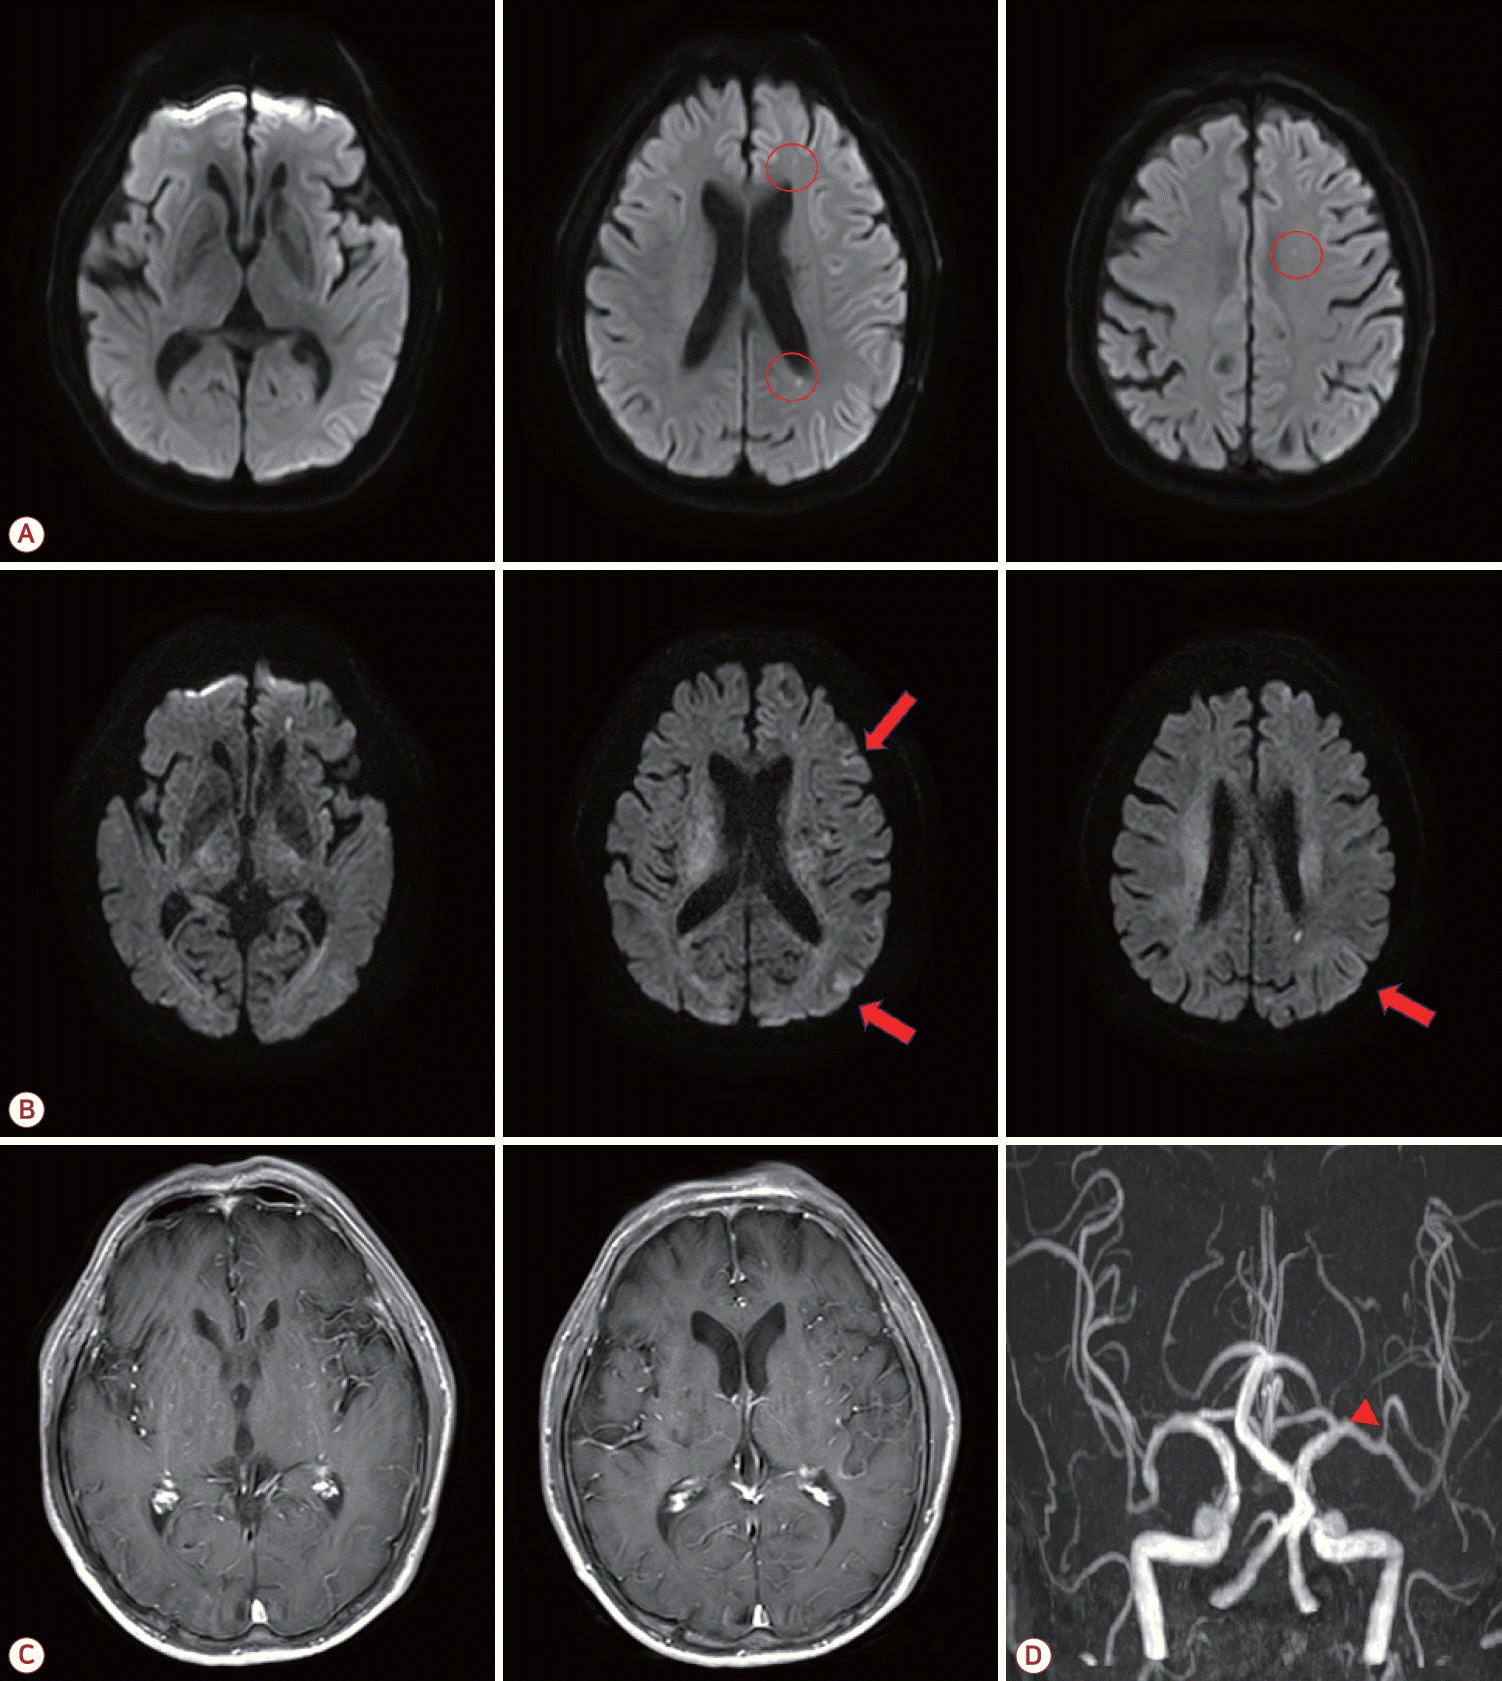

70세 남자가 초기 발열로 지역 응급 의료 센터에 방문하여 진료 중 추가 발열이나 경련 없이 실어증과 우측 근력 저하가 나타났다. 자기공명영상(magnetic resonance imaging, MRI) 확산강조영상에서 좌측 대뇌동맥 영역에 다발성 고신호강도의 병변이 확인되어 초급성 뇌경색의 치료를 위하여 본원 응급실로 증상 발생 4시간 만에 전원되었다(Fig. A).

Brain magnetic resonance imaging of the patient. (A) Initial diffusion-weighted imaging (DWI) revealed multiple small diffusion restrictions in the left cerebral hemisphere (red circles). (B) Follow-up DWI obtained after 3 hours revealed additional lesions and suspected high signal intensity in the left cerebral cortex (red arrows). (C) T1 gadolinium-enhanced imaging showed no prominent meningeal enhancement. (D) Magnetic resonance angiography revealed stenosis in the superior division of the left middle cerebral artery (red arrowhead).

증상 발생 4시간 40분에 추가로 진행된 확산강조영상에서 처음 확인된 뇌병변 이외에 대뇌 피질을 따라 고신호 병변이 추가로 확인되었다(Fig. B). T1 조영증강영상에서 뚜렷한 연수막 조영증강은 확인되지 않았다(Fig. C). 한달 전 뇌수막염으로 입원하여 진행한 뇌혈관영상과 비교하여 경미한 좌측 중대뇌동맥 위분지에 동맥경화가 악화 없이 확인되었다(Fig. D).